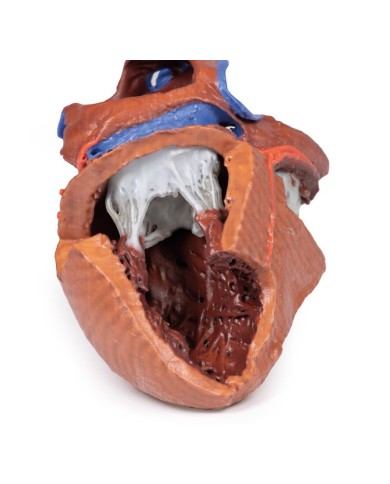

Modello di cuore di alta qualità scomponibile in 5 parti

Modello di cuore di alta qualità scomponibile in 5 parti

La parete anteriore del cuore è staccabile per poter vedere i ventricoli.

Realizzato in stampa 3D ad elevatissima risoluzione a colori.